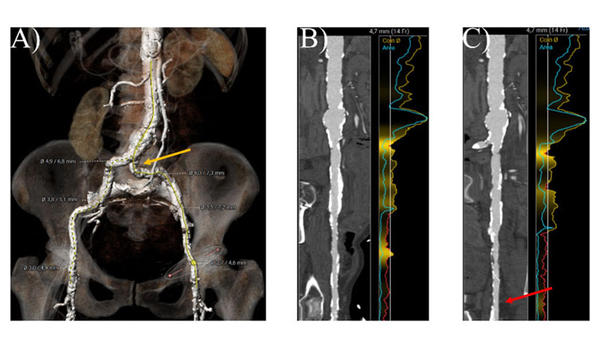

In diesem Fall zeigt die Computertomographie (CT) der Femoralgefäße eine zirkuläre Verkalkung an der Punktionsstelle der rechten Arteria femoralis communis (CFA) (Abbildung 1B) im Vergleich zu einer dorsalen Verkalkung nur an der linken CFA (Abbildung 1C, roter Pfeil). Beide A. iliaca externa zeigen eine Lumenverengung, und die A. iliaca communis links weist eine Kombination aus Knickung und Verkalkung auf (gelber Pfeil).

Abbildung 1. CT-Analyse des femoralen Zugangs. A) 3D-Rekonstruktion der Becken- und Femoralarterien B) gestreckte Ansicht der rechten Beckenachse C) gestreckte Ansicht der linken Beckenachse.

Wenn der alternative Zugang in diesem Fall nicht geeignet wäre, könnte nach einer adjuvanten Therapie zur Optimierung des Gefäßzugangs, wie z. B. einer Ballonangioplastie und der Verwendung einer ballonexpandierbaren Schleuse, ein Versuch mit einem linksen femoralen Zugang in Betracht gezogen werden. Die intravaskuläre Lithotripsie kann verkalkte Gefäße sicher modifizieren und das Vorschieben einer Schleuse mit großem Durchmesser erleichtern, wie in der Disrupt PAD III-Studie gezeigt wurde9. Das Vorliegen einer nur dorsalen Verkalkung (ventral keine Verkalkung) der linken CFA könnte macht den Erfolg eines Gefäßverschlusses auf der linken Seite vielversprechender als auf der rechten Seite machen.